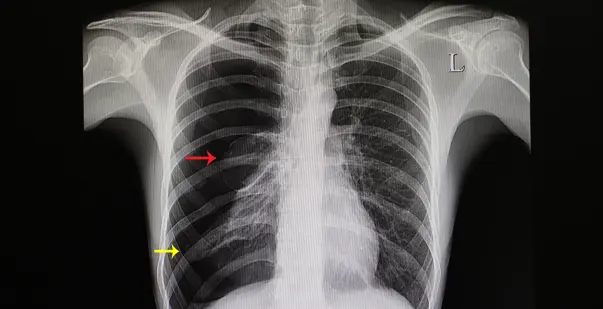

What is pneumothorax?

Air entering pleural cavity → lung collapse.

What is hemothorax?

Blood in pleural cavity.